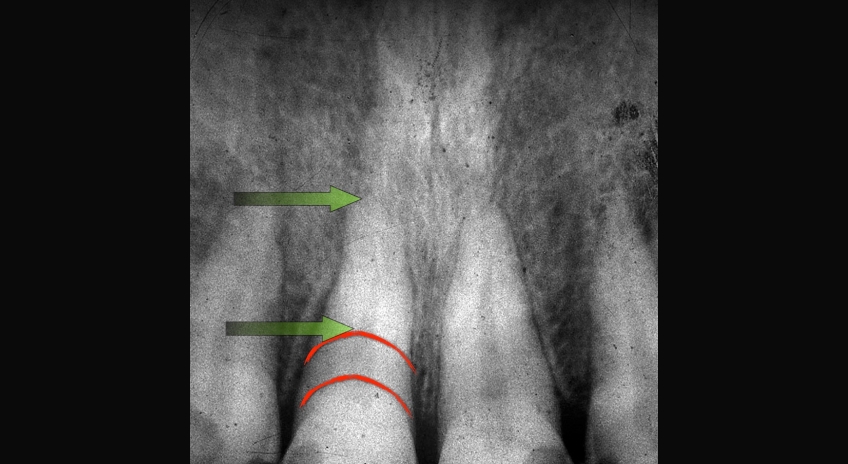

Your discussion should highlight the fact that as wear progresses, it will spread to more and more teeth in the mouth, making the potential treatment far more complex and expensive. It is also important to acknowledge that as tooth wear progresses, the teeth will often move — erupt, if you will — from dentoalveolar extrusion to maintain occlusal contact. This means the teeth are getting shorter and shorter and future treatment may involve possible crown lengthening to reposition gingiva and bone to expose more tooth (Figs. 1–5). If crown lengthening is necessary for a patient, Spear members can use the patient education video Crown Lengthening (Tooth Wear), which illustrates this well.

Examples of treatment options may be crown lengthening vs. intrusion to reposition overerupted anterior teeth (Figs. 6–10). You can explain each — or show the Spear Patient Education videos of each — then discuss with the patient why you believe one may be better for them.